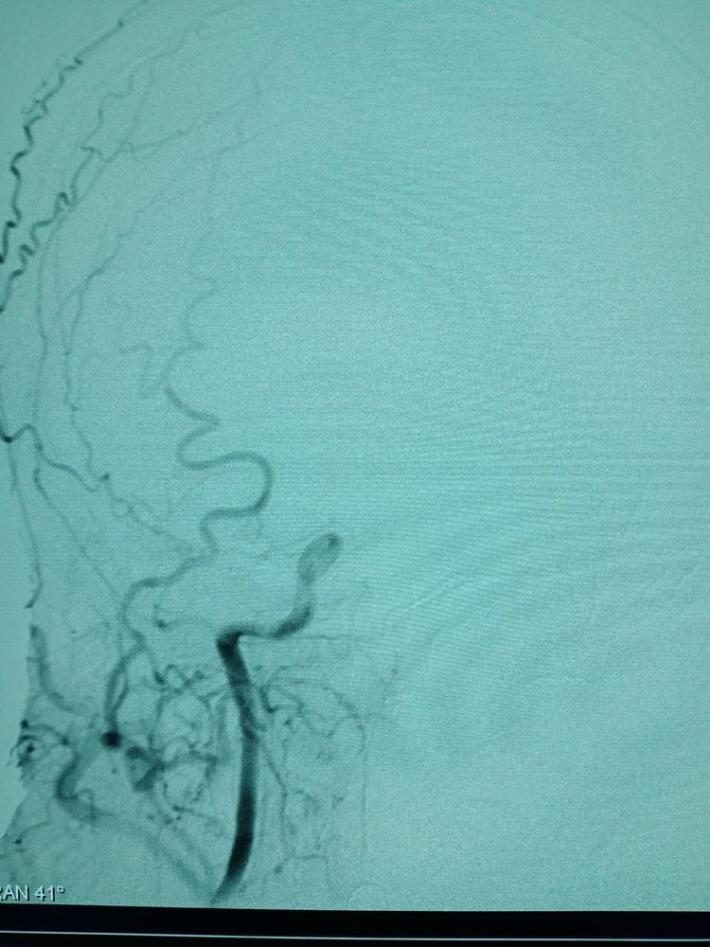

球囊扩张

球囊扩张后30分钟,重复造影,狭窄明显改善,前向血流TICI3级。